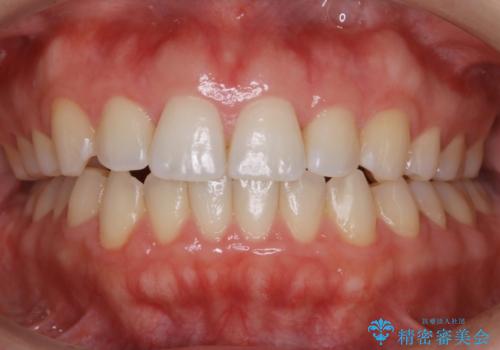

上下のデコボコを治したい インビザラインによる矯正治療